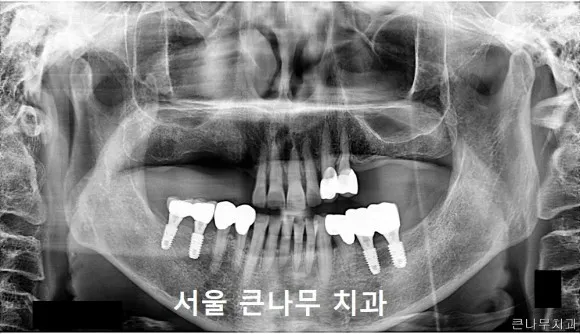

최종적으로 보철까지 들어간 모습입니다.

전후 사진으로 비교해보겠습니다.

전

후

상악(위턱)의 틀니도 수리하여 편안하게 사용할 수 있게 되었고, 하악(아래턱) 또한 네 개의 임플란트로 인해 어금니 없이 생활하시던 예전 모습에 비해 저작 기능을 회복하여 훨씬 높은 만족감을 느끼실 수 있었습니다.